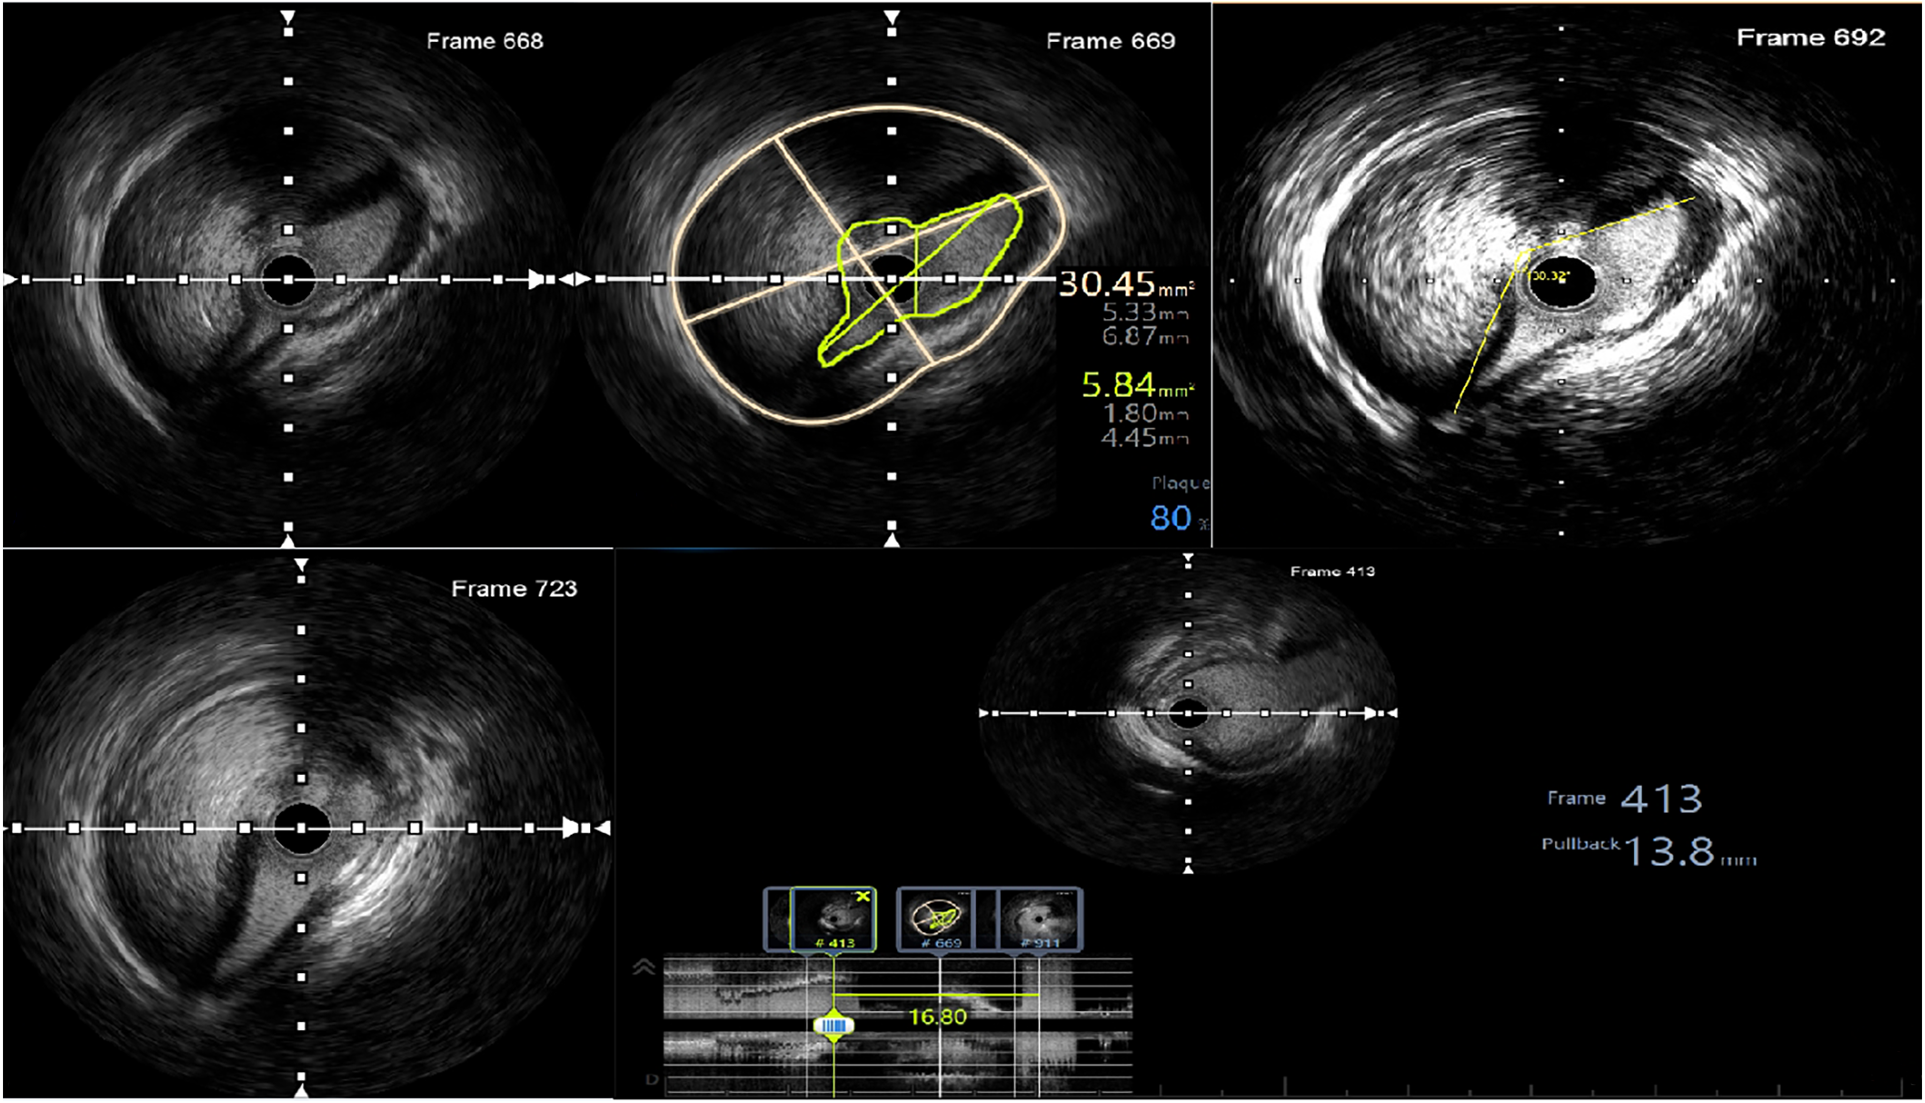

Coronary angiography was subsequently performed on the patient via the femoral artery approach. The result demonstrated severe stenosis of the LMCA, with dissection extending into the ostium of the LCx. No significant stenosis was observed in the LAD, RCA, or bypass grafts. Using a sion wire, the lesion in the distal LCx was successfully crossed, after which a sion blue wire was advanced towards the distal LAD (Figure 2).

Figure 2. Results of the coronary angiography. (A) Dissection extending from the LM to the LCx (indicated by red arrow). (B–E) No significant stenosis observed in the LAD, RCA, Ao-vein-LAD, and Ao-vein-RCA. (F) Passage of the wire through both the LAD and the LCx, accompanied by an IVUS assessment.

Afterwards, IVUS was used to assess the lesion. The findings indicated an absence of dissection in the LAD. However, examination of the LMCA to the LCx showed images suggesting complete separation of the intima-media from the adventitia, along with the presence of intramural hematoma. The initial dissection site extended approximately 16.8 mm from the ostium of the LMCA to the ostium of the LCx. The smallest true lumen area was measured at 5.84 mm2, resulting in an 81% stenosis compared to the vessel lumen area of 30.45 mm2. The dissection angle measured at this site was 230 degrees (Figure 3). The distal reference diameter of the landing zone was determined to be 4 mm (ranging from 3.85 to 4.14 mm), with a plaque burden of 22%.